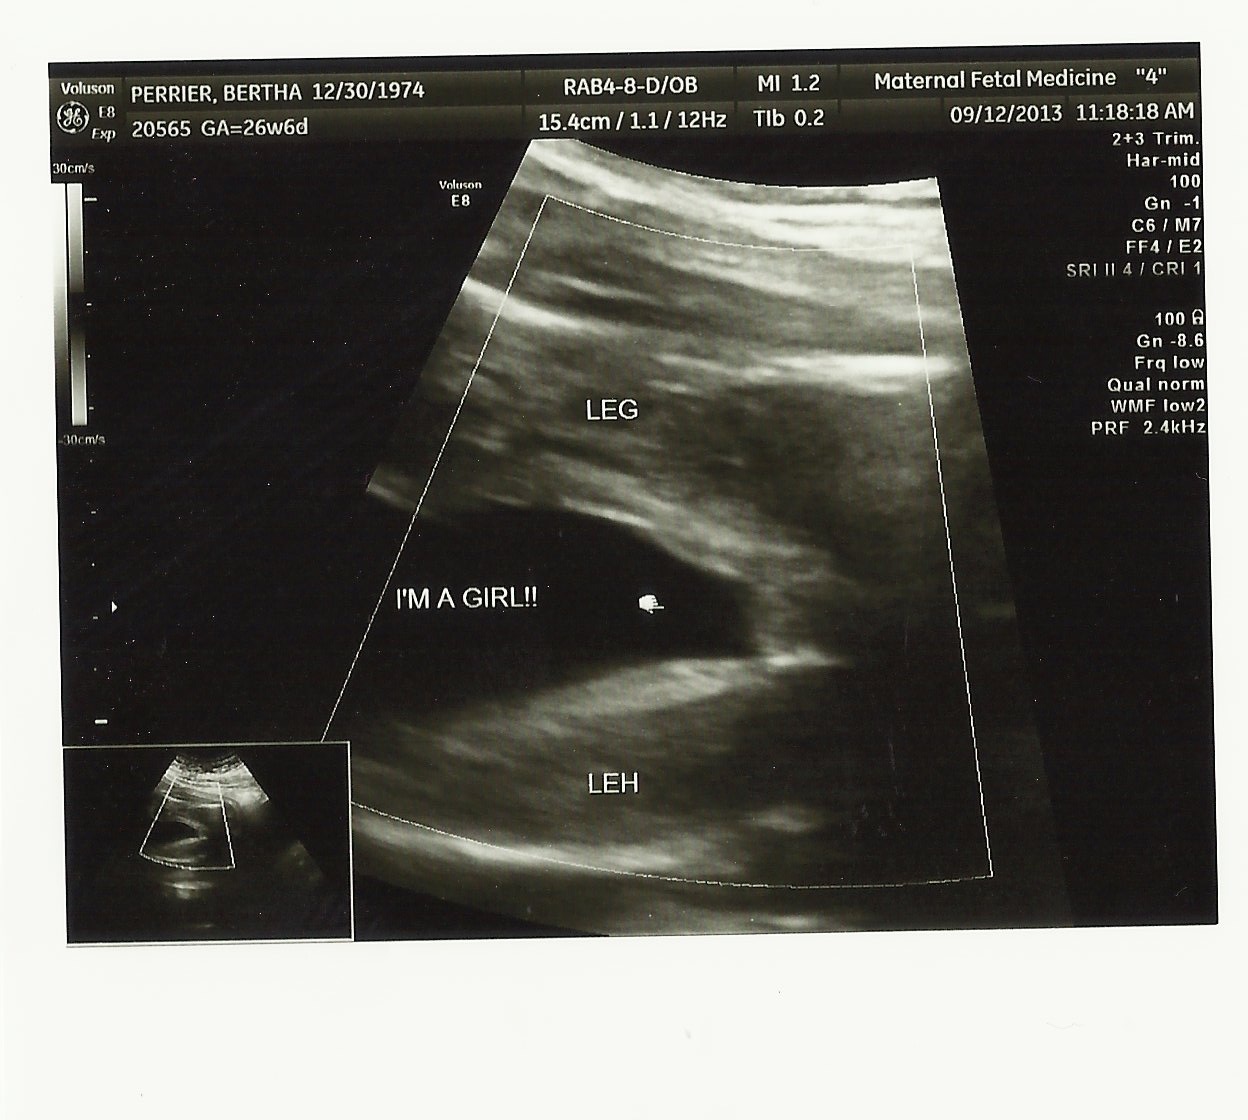

Confirmed today It's a Girl I will post another pic later Need to scan :DD:

!!!!Attachment 14009

My baby girl

Attachment 14025